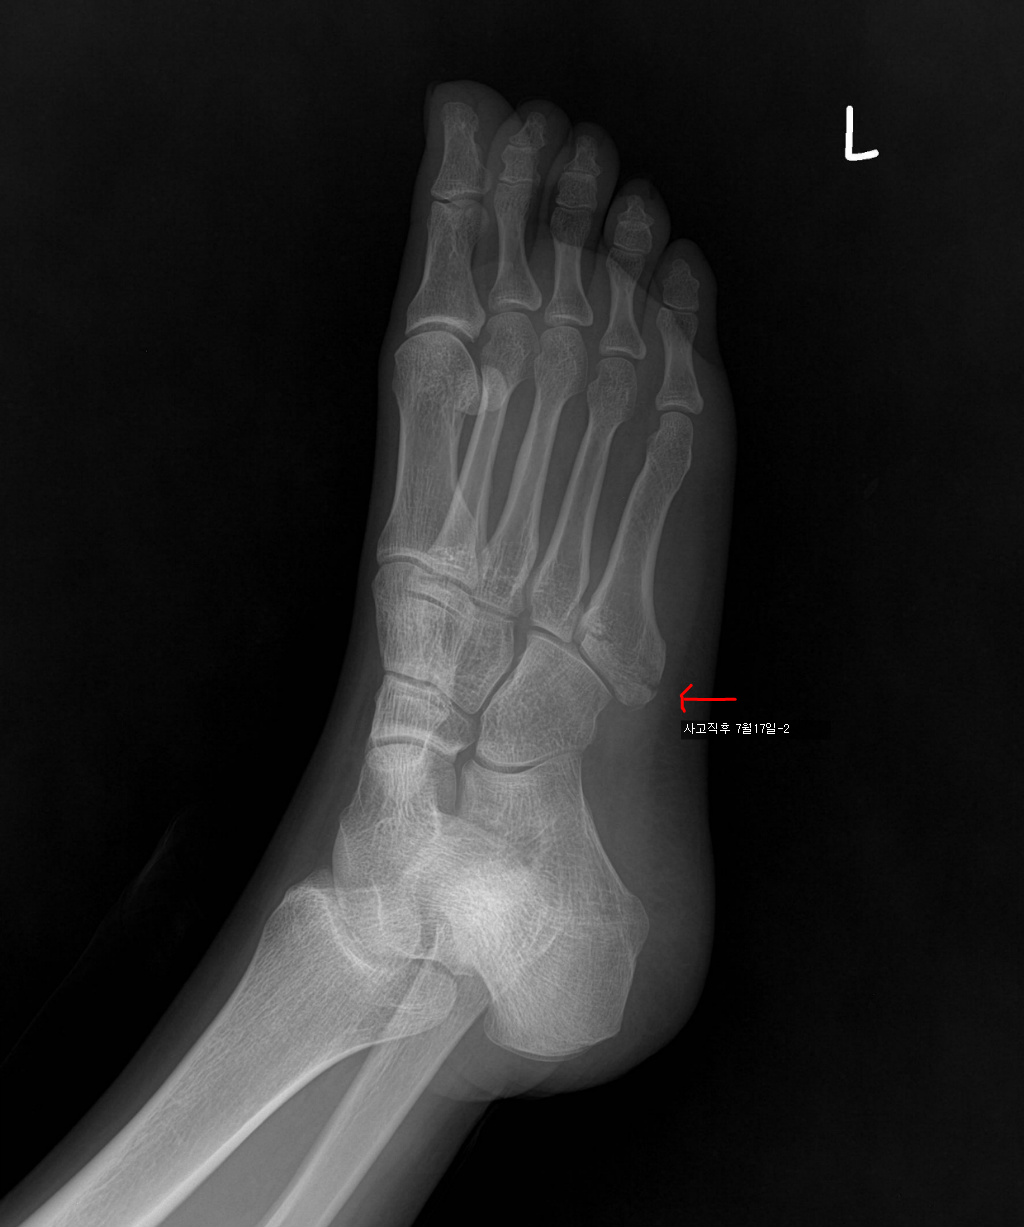

7/17 : 출근 중 지하철 계단에서 구르는 사고로 좌측제5중족골기저부 골절

7/18 : 관헐적 정복 및 금속내고정술  시행 및 반깁스 (2주)

아래는 그간의 사진입니다. 제 눈은로는 수술직후의 사진과 3개월후의 사진의 차이를 잘 모르겠네요..